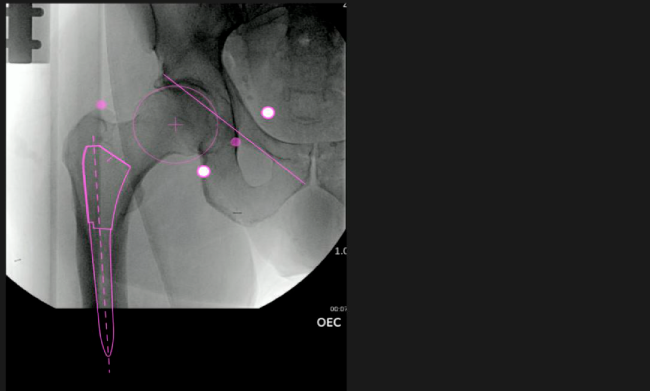

Nuestro sistema de navegación digital VELYS HIP NAVIGATION ™ para cirugía de cadera, es una tecnología innovadora y no invasiva diseñada para apoyar la toma de decisiones de los médicos en tiempo real y basada en datos; aumentando la precisión y dando mejores resultados.

El sistema de navegación digital VELYS HIP NAVIGATION ™ para cirugía de cadera, es una tecnología innovadora y no invasiva diseñada para potencializar la toma de decisiones en tiempo real y basada en datos; aumentando la precisión y mejorando los resultados a corto, mediano y largo plazo para los pacientes.

Planeación preoperatoria mediante la creación de plantillas digitales para reemplazo de cadera y análisis intraoperatorio

Inclinación y anteversión de la copa acetabular para una correcta colocación del implante.

Desplazamiento y offset para posicionamiento óptimo del componente (vástago) femoral.

Verificación de la posición deseada del implante que potencialmente puede ayudar a reducir la probabilidad de dislocación protésica y aumentar la estabilidad de la articulación.

Anotaciones digitales y herramientas de análisis de longitud de pierna.

Con tecnología ONETRIAL® que calcula automáticamente el cambio en la longitud de la pierna y el desplazamiento para todas las combinaciones de implantes en una tabla fácil de leer.